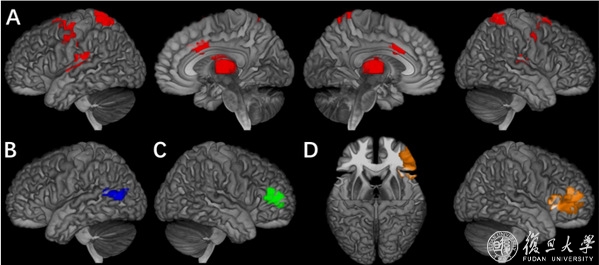

研究团队将“外向障碍”的症状分为四个行为域,即多动、冲动、注意力缺陷和品行问题,并找到其各自在奖赏预期和行为抑制任务中显著相关的核心脑区,这些行为域各自对应的核心脑区不仅在不同的行为域间具有显著的区别,并且指向了可能的共病机理。

图示:A)奖赏预期下的多动行为核心脑区;B)行为抑制任务下的冲动行为核心脑区;C)行为抑制任务下的注意力缺陷核心脑区;D)行为抑制任务下的品行问题的核心脑区。